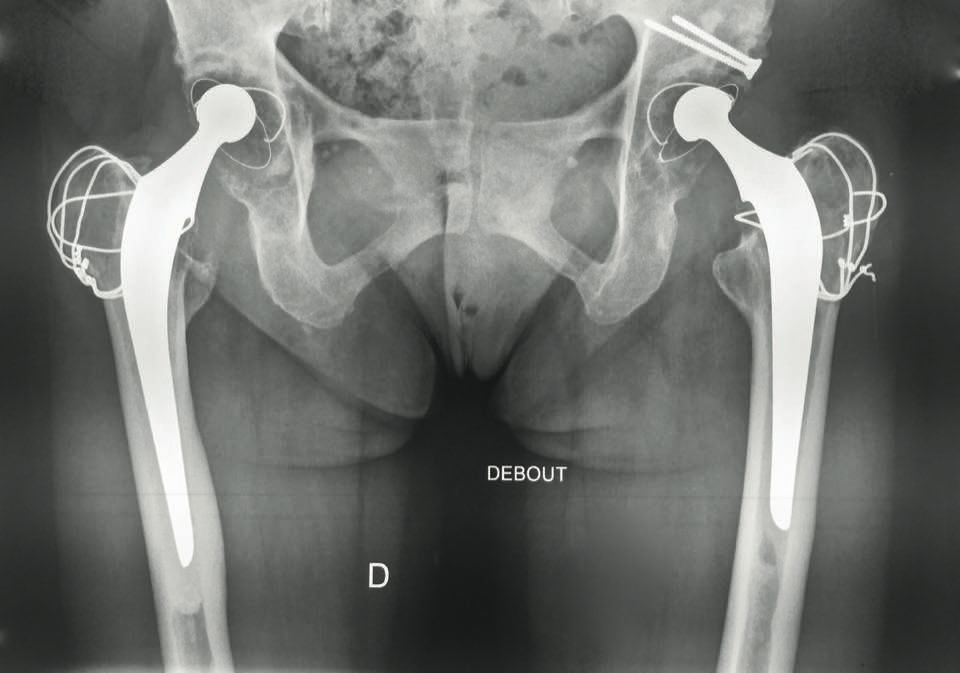

Technique Technique de Reconstruction Cotyloïdienne par armature de Kerboull et allogreffe , Luc Kerboull Espace Médical Vauban, Paris, France , Moussa Hamadouche Centre Hospitalo-Universitaire Cochin Port-Royal - Hôpitaux de Paris, Paris, France , Marcel Kerboull Centre Hospitalo-Universitaire Cochin Port-Royal, Assistance Publique - Hôpitaux de Paris, Paris, France N°268 - Novembre 2017 - Cahier 1 ● 17 min de lecture